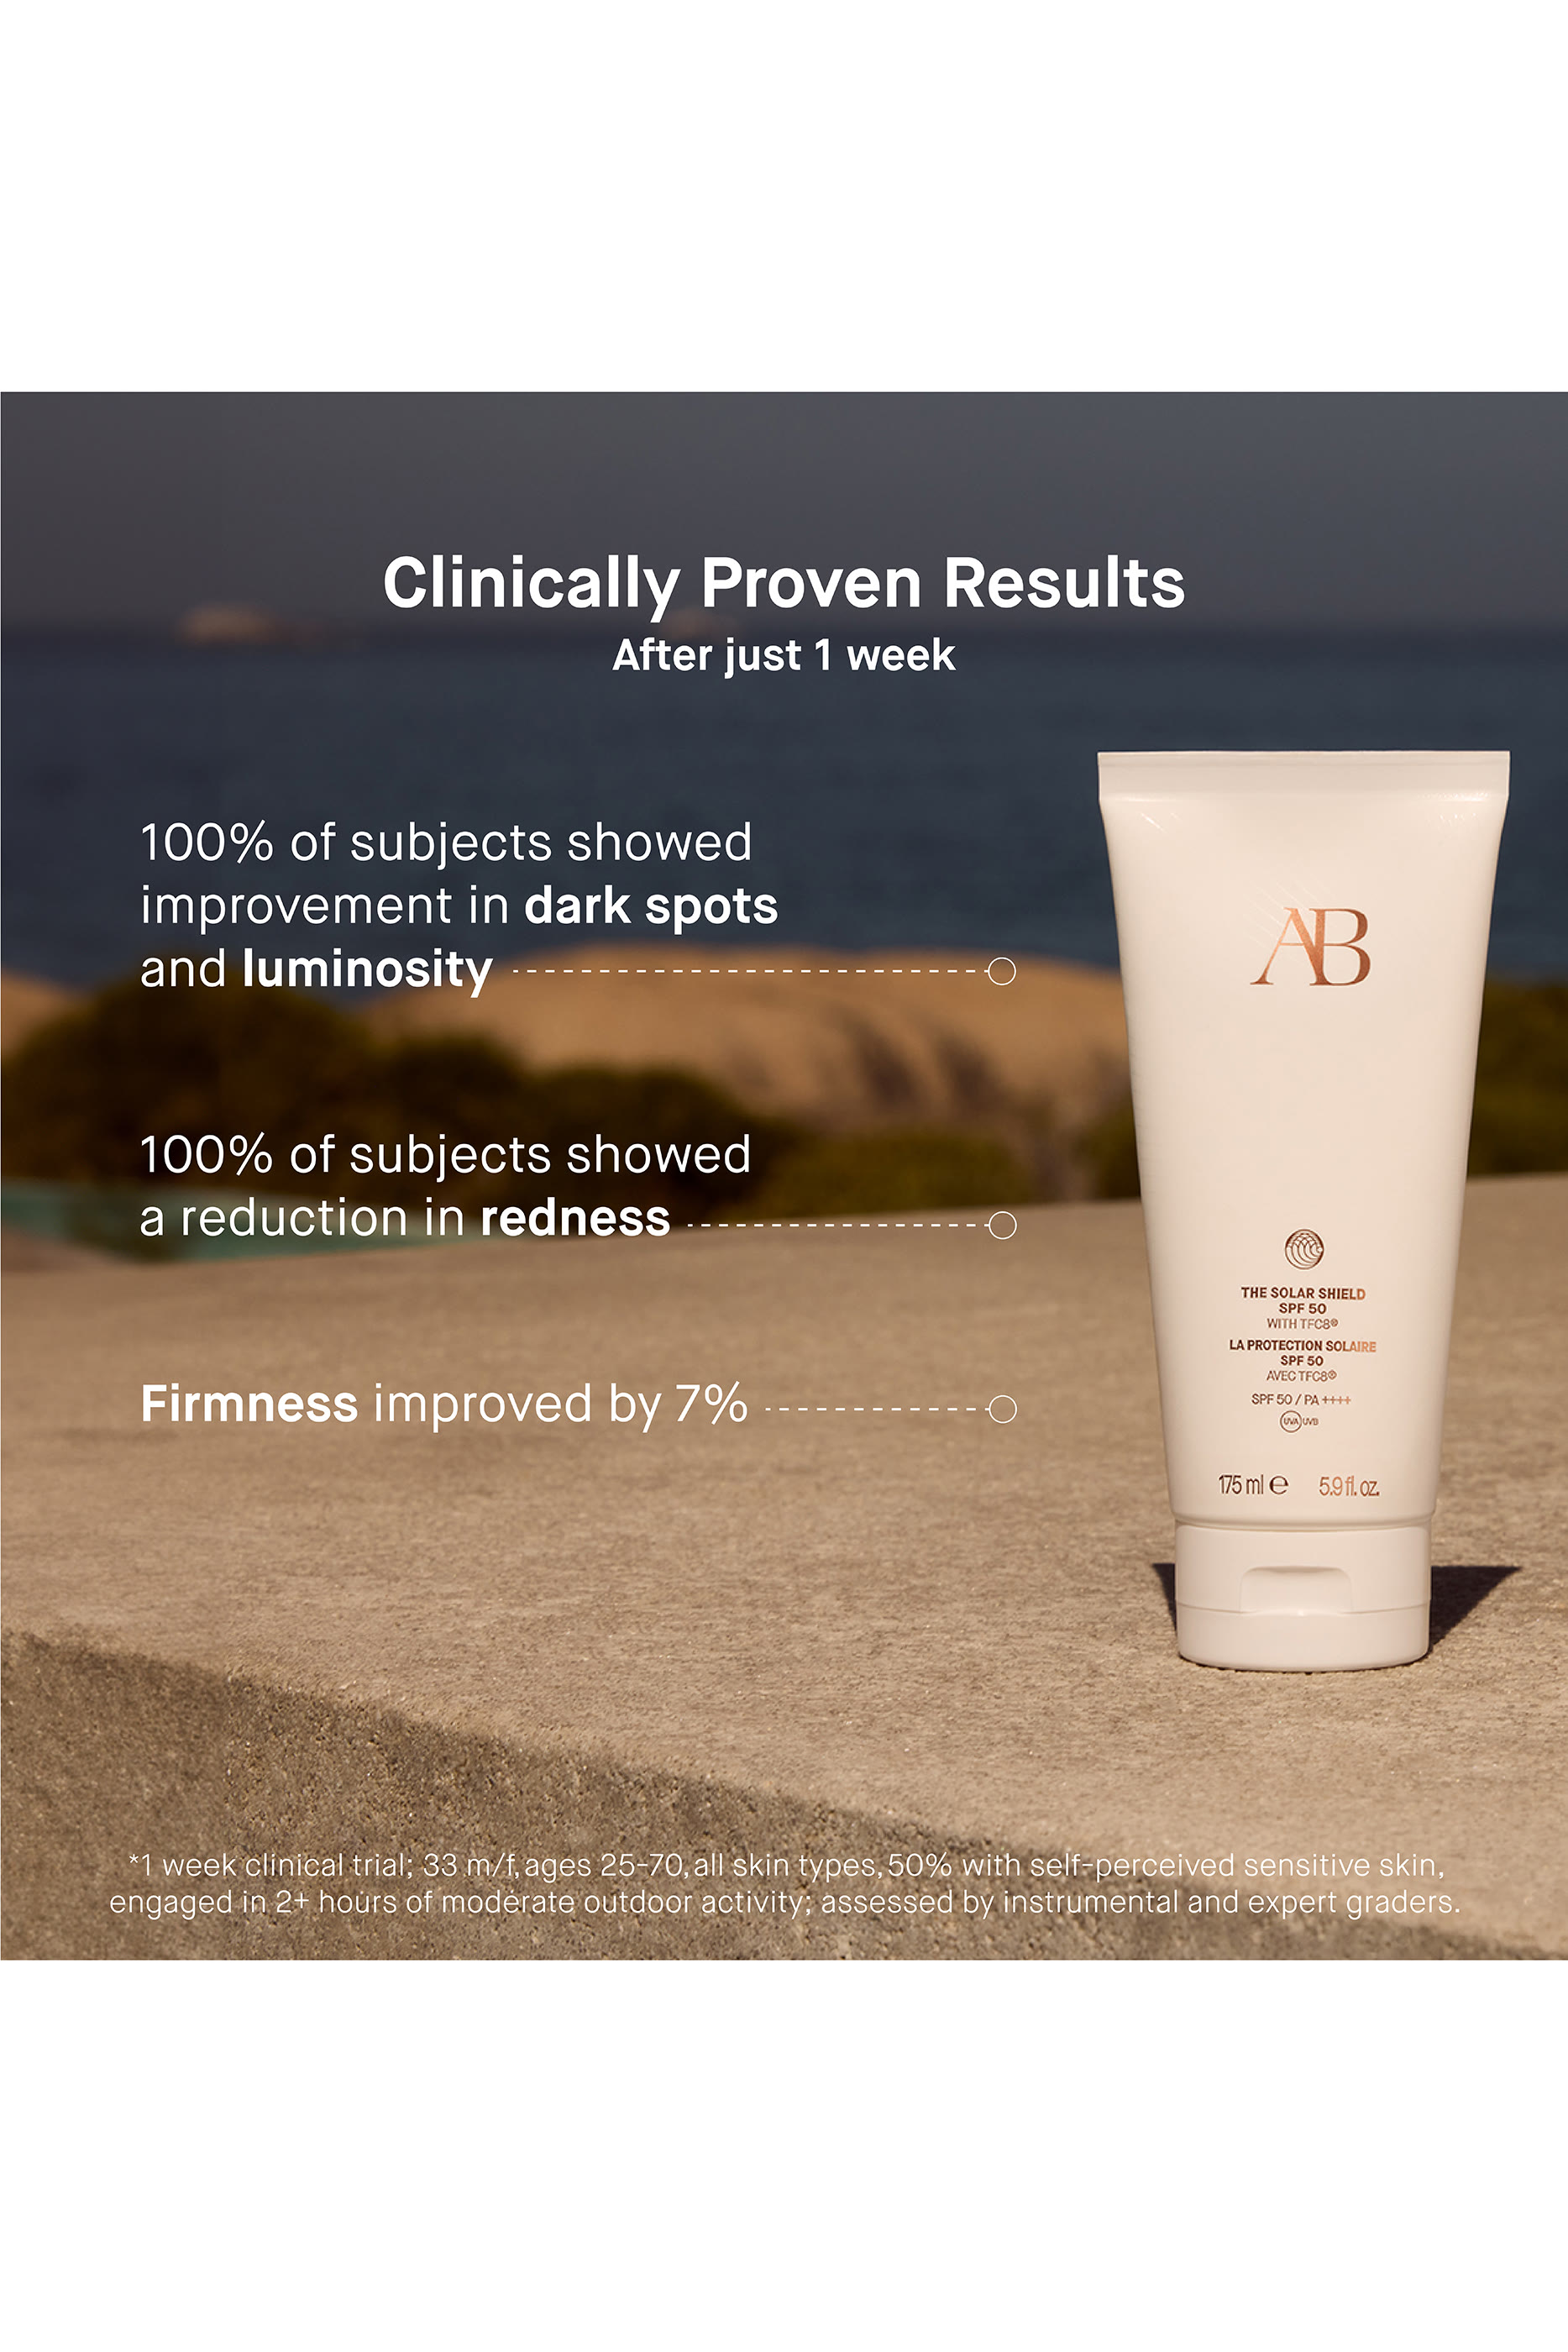

The innovative skincare line Augustinus Bader arrives at Bloomingdales. Developing skincare that supports the body's natural renewal process and reduces damage caused by environmental influences. The products are based on one principle: our body knows best how to heal itself. Cells already know what it takes to heal all sorts of skin ailments. Be it wrinkles, acne, redness, dry patches, or pigmentation spots… the solution to all these problems lies dormant in the body. Our cells just need a "push" to heal themselves. Professor Bader has developed and patented this new drive for our cells himself. The midnight blue bottle is now in many bathrooms and is one of the products that enjoy an incredible hype among many Hollywood stars. Augustinus Bader Dubai creates a more youthful, radiant complexion.